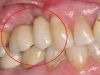

• коронки установленные на имплантаты

Здоровая десна вокруг импланта

Цирконий естественно взаимодействует с десной, мягкие ткани прекрасно с ним контактируют, плотно прилегая без раздражений.